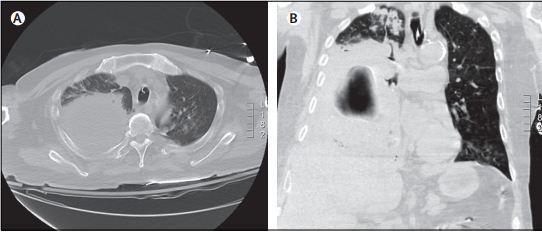

脓胸CT

脓胸ct表现